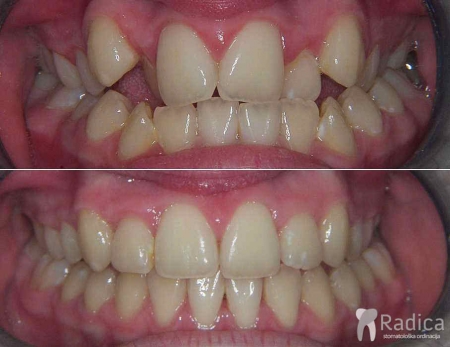

Kompresija – fiksna ortodontska terapija bez ekstrakcije (vađenja) zuba:

Kompresija – fiksna ortodontska terapija bez ekstrakcije (vađenja) zuba.

U terapiji je korišten i headgear te se napravio „striping – aproksimalna redukcija cakline “ donjih frontalnih zuba: